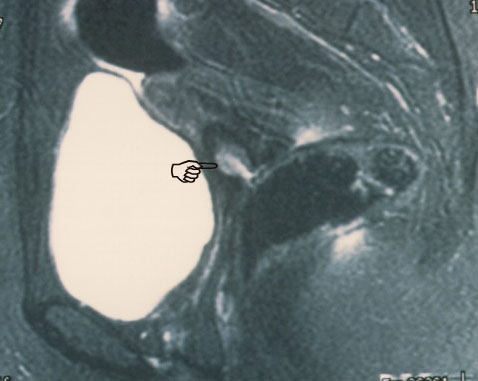

fig. 1

Figura 1.- RMN: Plano sagital en el que se ve el endocervix (punta de dedo) engrosado, de color claro, bien delimitado y con un probable tapón de moco en la luz. Esta imagen ovalada del endocervix es totalmente superponible a la imagen macroscópica (ver foto macro).